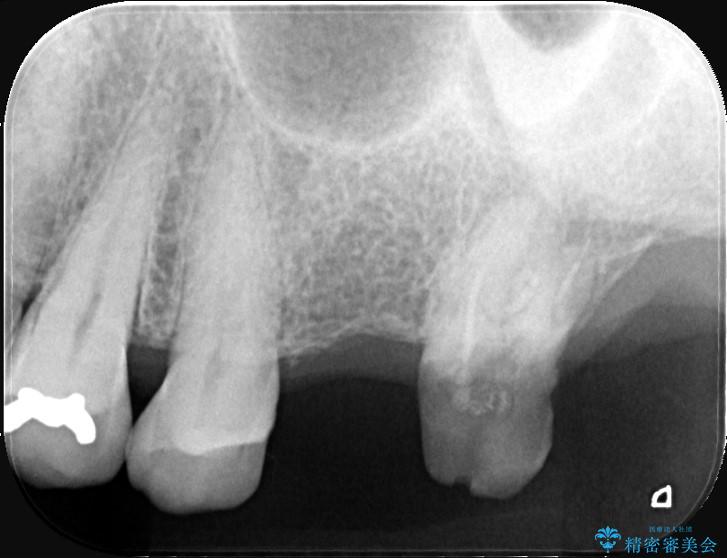

精密検査の結果、治療を中断していた左上7番は重度の虫歯や歯周組織の崩壊により保存が難しい状態でした。

6番も歯を失ってから時間が経っていたため、奥歯でしっかりと噛むことができない状態でした。

7番については抜歯と同時にインプラントを埋入する「抜歯即時埋入法」を選択。通院回数と治療期間を大幅にカットすることで患者様の負担を減らします。

あわせて6番目にもインプラントを行い、奥歯でしっかり力強く噛める状態を整える計画です。